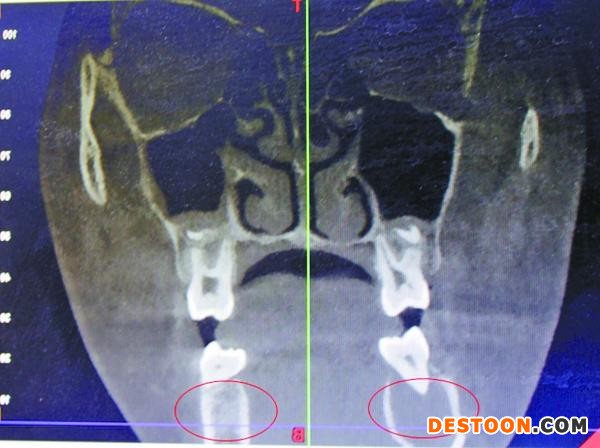

受血管瘤影響,右頜骨發(fā)生病變

據(jù)口腔醫(yī)院醫(yī)生王琨介紹,4月7日,在采取措施止血后,院方迅速為小玉進行了一系列檢查,發(fā)現(xiàn)其患的是一種非常罕見的頜骨中央性血管瘤。“下牙槽里的動脈血管發(fā)生病變,長了若干細微的支血管,將她的頜骨破壞后發(fā)生出血。”

保留部分頜骨 女孩留住美麗

宋慶高博士說,受血管瘤病變影響,女孩的右頜骨,已經(jīng)形成8×2.5厘米大小的腔竇,“相當于一個空洞。”從方便手術考慮,完全可能將她右側(cè)頜骨去掉,但那樣會形成面部缺陷,影響美觀,而且右側(cè)無法長牙。